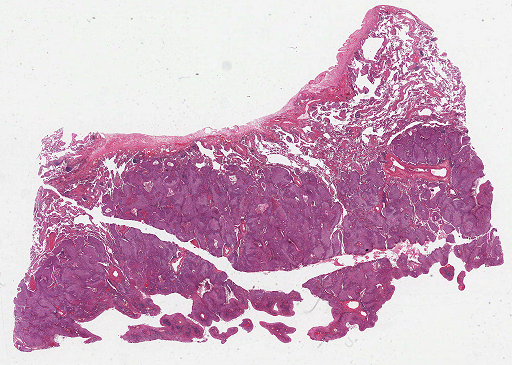

For qualitative ROI detection evaluation check Fig. 3.

Refer to caption

(a)

(b)

Figure 3: Qualitative view of ROIs recognized by Suffy through its Patch Classification. (a) An example WSI from the test set of the CAMELYON16 dataset [3]. (b) ROIs are identified by Snuffy with black lines delineating the ground truth ROIs.